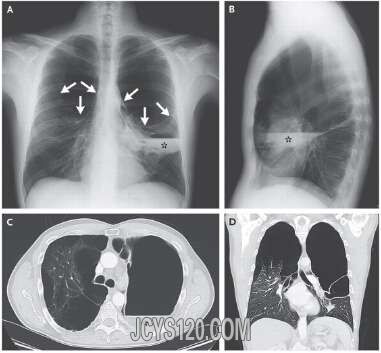

• 反复咳嗽咳痰八个月:并不是肺炎 attach_img agree

• 反复咳嗽咳痰八个月:并不是肺炎 患者女性,73岁,家庭主妇,因“反复咳嗽咳痰8个月,痰中带血1个月”于2010年9月9日入院。 患者于8个月前无明显诱因出现咳嗽,以晨起明显,咳白色黏痰,量不多,无发热,无胸 ...  阅读全文>